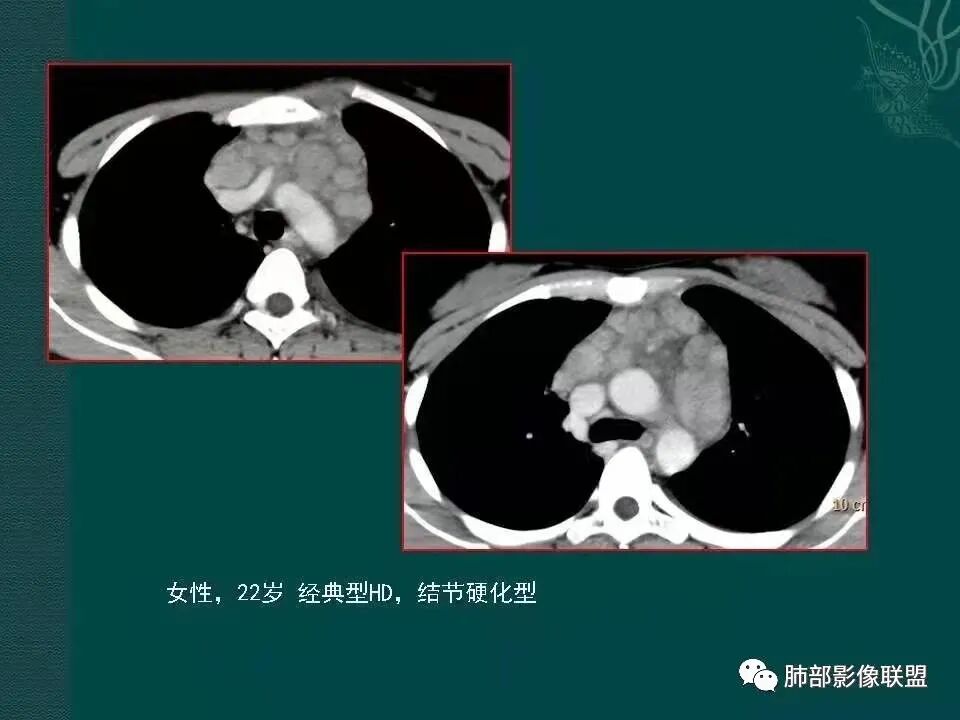

1、临床特点:19岁男性,发现双肺结节,实验室检查无特殊。

2、影像特点:两肺可见多发大小不一的结节影,部分结节周围可见晕征,部分结节沿着支气管血管束分布,部分位于胸膜下。前纵隔内可见多发结节样软组织密度影,边界不清,部分病灶融合倾向,其脂肪间隙显示模糊。由于腹腔层面少,未能确定腹腔内有无增大淋巴结,需要连续层面追踪观察。

3、病例小结:年轻男性+前纵隔多发结节样软组织影+双肺多发结节,需要警惕淋巴瘤,至于多数老师提到鉴别结节病,结节病以双肺门对称性淋巴结肿大为典型表现,其肺内表现多为沿肺门旁支气管血管周围间质分布的多发结节,结节病可表现纵隔内多发淋巴结肿大、且淋巴结密实,孤立少融合,该病例中均缺乏以上特点,另外结节病好发中青年女性,此病例年龄亦不符合。